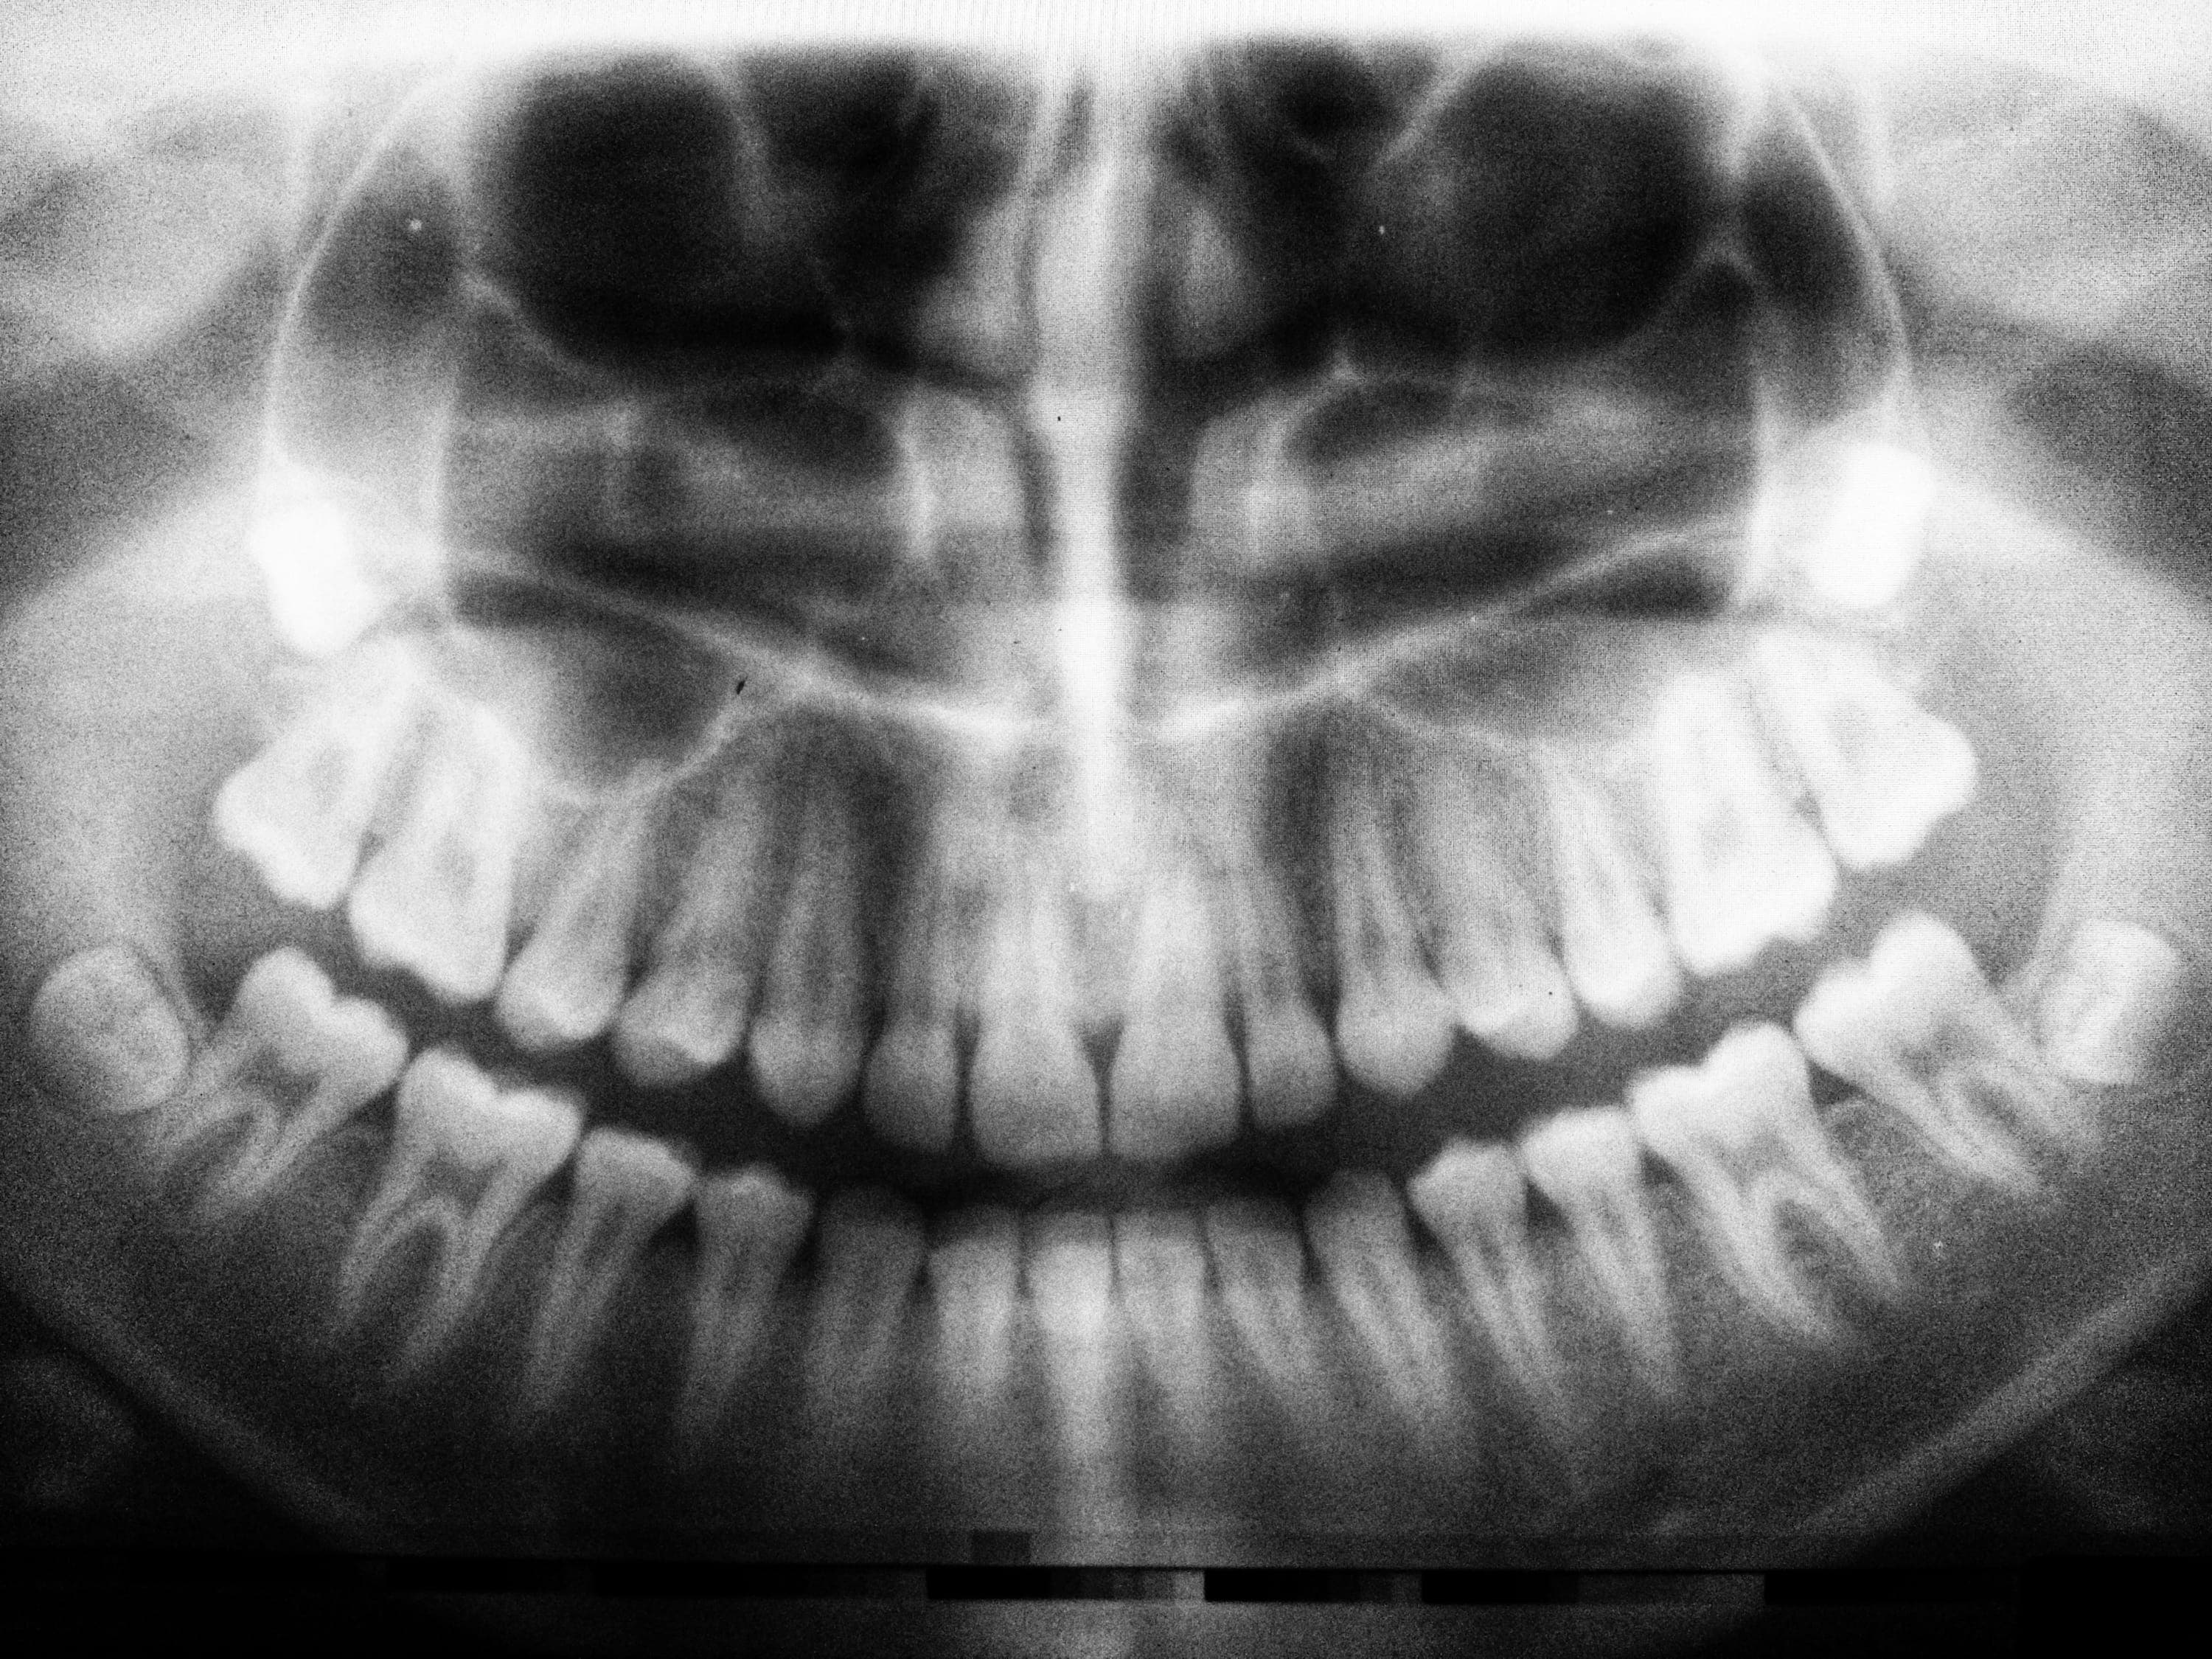

Panoramic X-Ray

Our panoramic X-rays give us a full view of your upper and lower jaws in a single image. This essential diagnostic tool allows us to evaluate wisdom teeth, TMJ issues, and orthodontic needs, as well as detect issues that might not be visible to the naked eye.